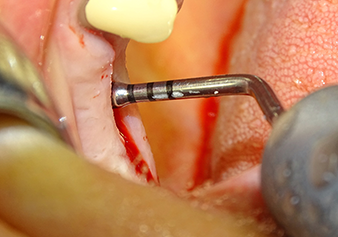

The implant bed is widened to 3.0 mm with the I3A instrument

Fig.5: In the next step, the implant bed is widened to 3.0 mm with the I3A instrument (power 100%, coolant 80%). The depth marks reliably prevent the preparation from going too deep.